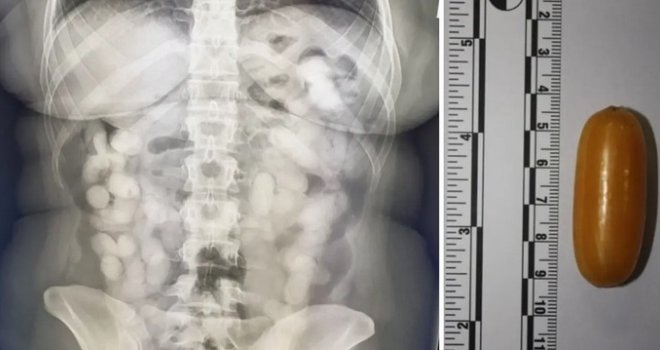

Brazilka (28) u Zagreb je stigla letom iz Sao Paula preko Lisabona. Bila je sumnjiva pa su joj rendgenom snimili abdomen. Odmah su je prebacili u bolnicu. U sebi je imala čak 76 kapsula s drogom

U Zagreb je stigla letom iz Sao Paula preko Lisabona. Carinicima je bila sumnjiva pa su joj napravili rendgen abdomena. Vidjeli su više stranih tijela i odmah je prebacili u bolnicu.

Tamo su iz nje izvadili čak 76 kapsula s drogom koja teži otprilike 990 grama, objavila je zagrebačka policija.

Prilikom obavljanja carinskog nadzora, putnica je podvrgnuta nadzoru u sklopu kojeg je učinjen rengenski snimak abdomena te je na istom bio vidljiv veći broj stranih tijela u probavnom traktu osumnjičene.

Tijekom boravka u bolnici opravdana je sumnja carinika i policajaca te je dokazano da je u tijelu prenosila ukupno 76 komada kapsula ispunjenih drogom kokain, koje je prethodno progutala u Brazilu.

Droga koja je na taj način unesena u Republiku Hrvatsku ukupne je težine oko 990 grama.